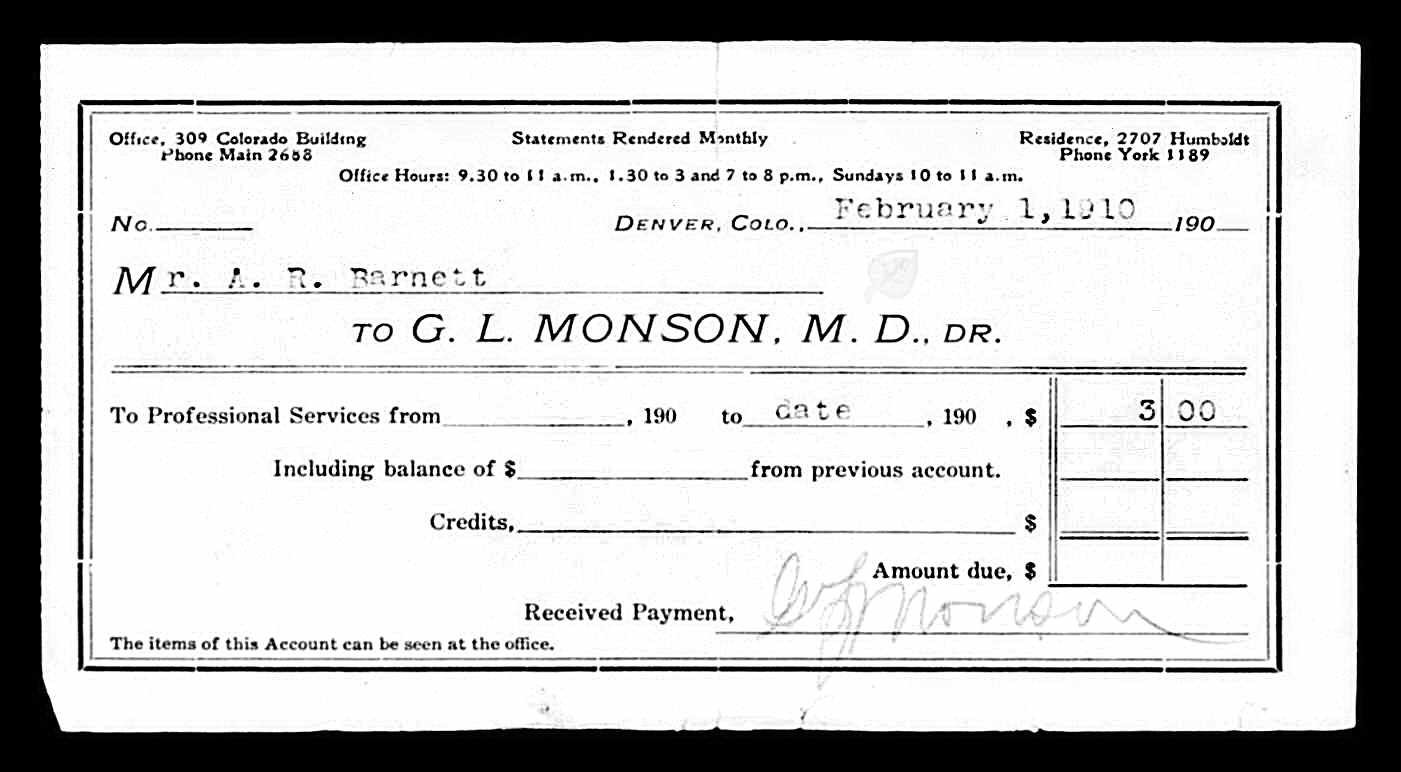

Died: March 4, 1910 in Denver, Denver County, Colorado.